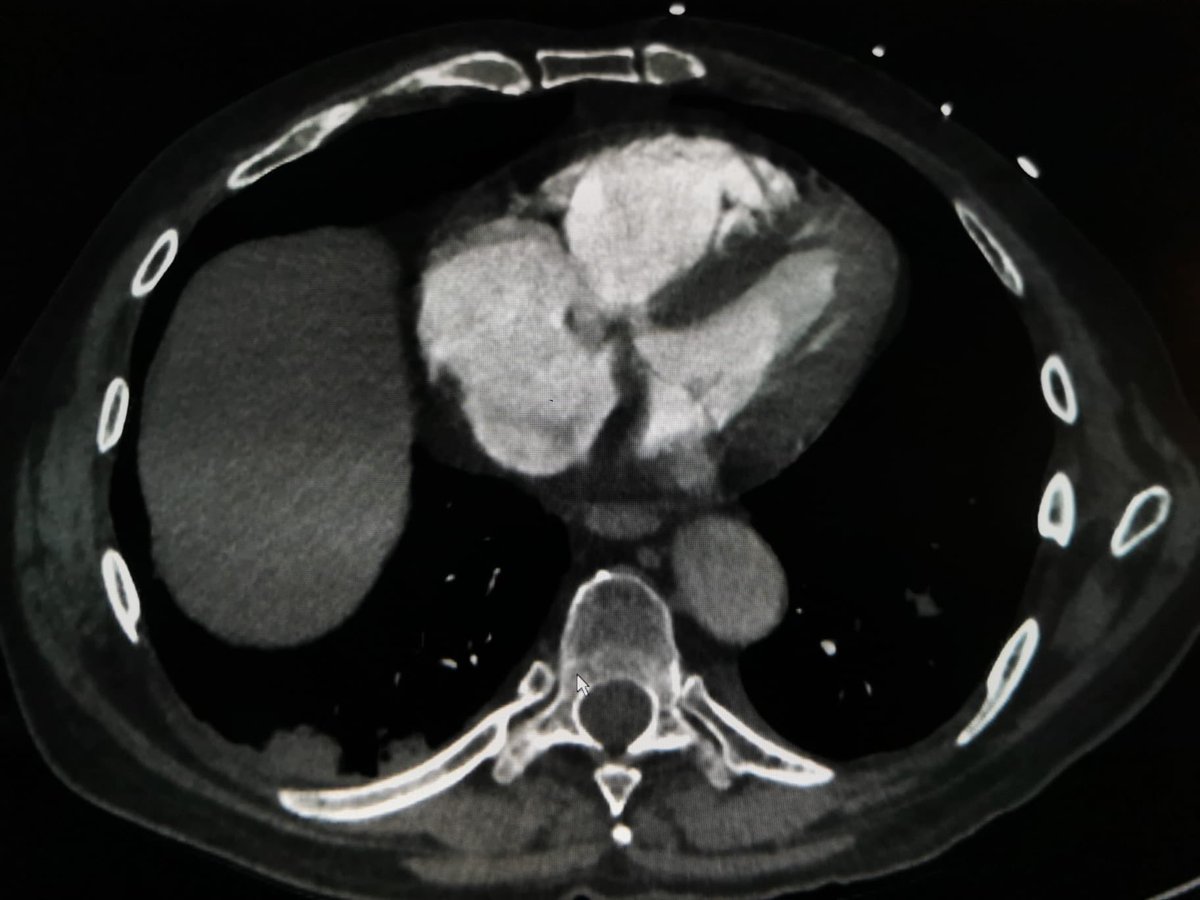

Varón de 72 años, previamente sano que acude esta madrugada por disnea…

8

36

310